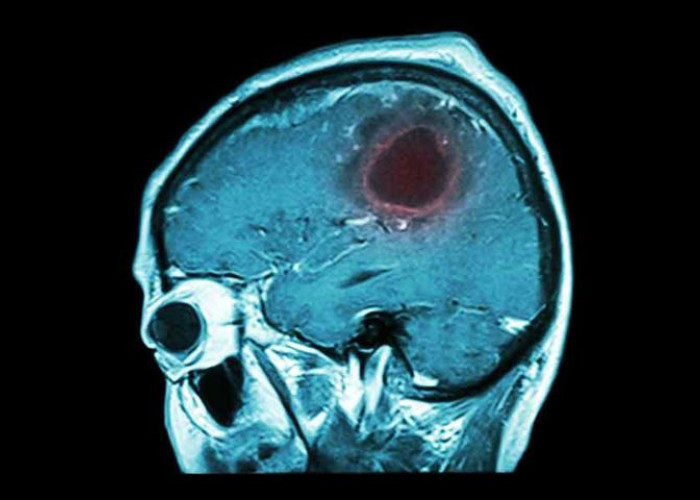

Υγεία ΚΑΡΚΙΝΟΣ ΤΟΥ ΤΡΑΧΗΛΟΥ ΤΗΣ ΜΗΤΡΑΣ: ΤΑ ΣΗΜΑΔΙΑ ΟΤΙ Η ΘΑΝΑΤΗΦΟΡΑ ΑΣΘΕΝΕΙΑ ΕΧΕΙ ΠΡΟΧΩΡΗΣΕΙ! 25 Ιαν 2019, 13:35